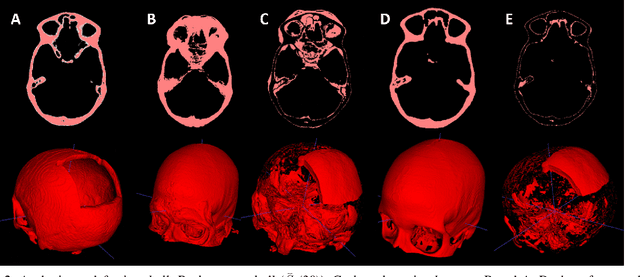

Abstract:Designing implants for large and complex cranial defects is a challenging task, even for professional designers. Current efforts on automating the design process focused mainly on convolutional neural networks (CNN), which have produced state-of-the-art results on reconstructing synthetic defects. However, existing CNN-based methods have been difficult to translate to clinical practice in cranioplasty, as their performance on complex and irregular cranial defects remains unsatisfactory. In this paper, a statistical shape model (SSM) built directly on the segmentation masks of the skulls is presented. We evaluate the SSM on several cranial implant design tasks, and the results show that, while the SSM performs suboptimally on synthetic defects compared to CNN-based approaches, it is capable of reconstructing large and complex defects with only minor manual corrections. The quality of the resulting implants is examined and assured by experienced neurosurgeons. In contrast, CNN-based approaches, even with massive data augmentation, fail or produce less-than-satisfactory implants for these cases. Codes are publicly available at https://github.com/Jianningli/ssm

Abstract:Medical images, especially volumetric images, are of high resolution and often exceed the capacity of standard desktop GPUs. As a result, most deep learning-based medical image analysis tasks require the input images to be downsampled, often substantially, before these can be fed to a neural network. However, downsampling can lead to a loss of image quality, which is undesirable especially in reconstruction tasks, where the fine geometric details need to be preserved. In this paper, we propose that high-resolution images can be reconstructed in a coarse-to-fine fashion, where a deep learning algorithm is only responsible for generating a coarse representation of the image, which consumes moderate GPU memory. For producing the high-resolution outcome, we propose two novel methods: learned voxel rearrangement of the coarse output and hierarchical image synthesis. Compared to the coarse output, the high-resolution counterpart allows for smooth surface triangulation, which can be 3D-printed in the highest possible quality. Experiments of this paper are carried out on the dataset of AutoImplant 2021 (https://autoimplant2021.grand-challenge.org/), a MICCAI challenge on cranial implant design. The dataset contains high-resolution skulls that can be viewed as 2D manifolds embedded in a 3D space. Codes associated with this study can be accessed at https://github.com/Jianningli/voxel_rearrangement.